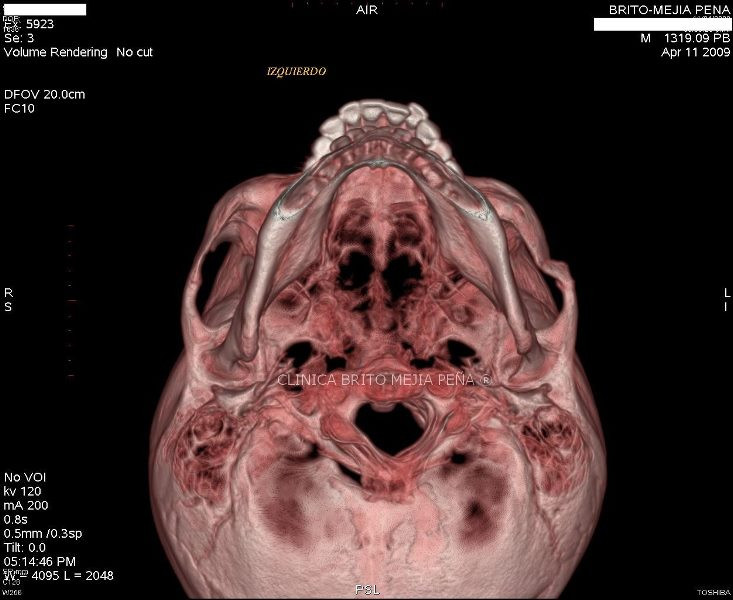

Fractura malar